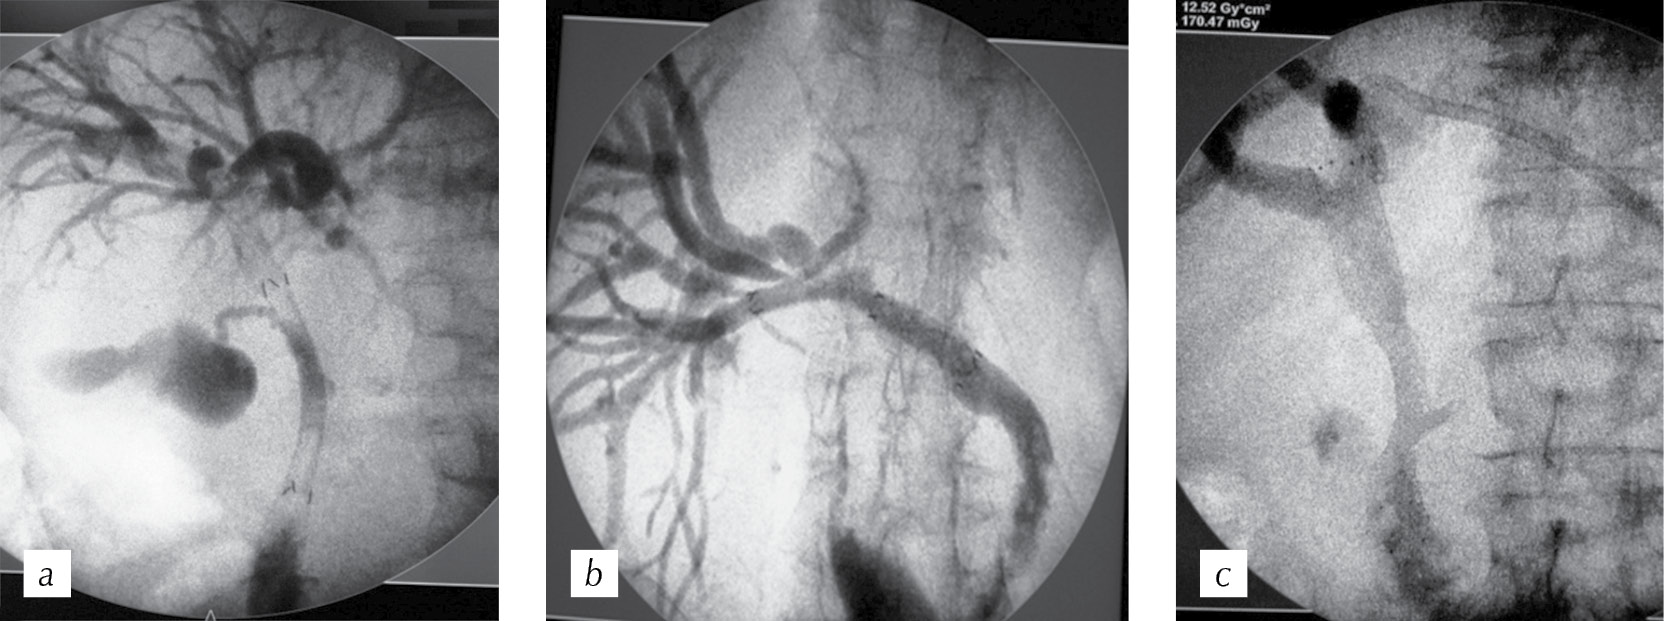

The main issues that we focused on when performing stenting were the presence of a functioning gallbladder, the joint return of the CBD and MPD, and the features of return of the segmental bile ducts (Fig. 1). At the beginning of the technique development, all the above anatomical aspects acted as “deterrents” to the use of coated SNSs. Gradually, we abandoned uncoated stents because of their rapid obstruction in the presence of tumor tissue invasion through stent cells and the relapse of jaundice. Figure 1 presents cases of stenting with partially covered nitinol stents in the case of a tumor lesion of the extrahepatic bile ducts, considering special aspects of the anatomy of the biliary tree and the area of the major duodenal papilla. For each patient, the nitinol stent was selected individually depending on the extent of the stricture, its location, and the above anatomical aspects. The correct choice of stent length and diameter are important factors in preventing its early obstruction and migration. The necessary length of the stent is the sum of the length of the stricture itself in addition to 2 cm (preferably 3 cm, if anatomy permits that) in the proximal direction, and 1 cm distally in the case of a suprapapillary installation, or 2 cm in case of a transpapillary installation.

Fig. 1. Stenting options for partially coated self-expanding nitinol stents considering the volume of anatomical features: a — the presence of a functioning gallbladder; b — stenting of the right lobar duct with extensive tumor lesion; c — joint infusion of the common bile duct and main pancreatic duct

Рис. 1. Варианты стентирования частично покрытыми саморасправляющимися нитиноловыми стентами с учетом анатомических особенностей: a — наличие функционирующего желчного пузыря; b — стентирование правого долевого протока при обширном опухолевом поражении; c — совместное впадение общего желчного протока и главного панкреатического протока